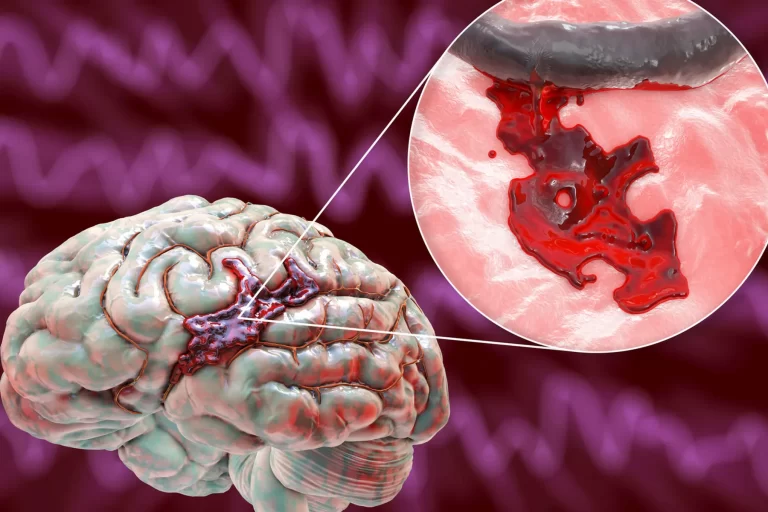

ورم مغزی یک آسیب شناسی جدی است که با تجمع غیرطبیعی مایعات داخل سلولی و خارج سلولی در سیستم عصبی مرکزی مشخص میشود و پیامد خطرناک آن افزایش حجم مغز و فشار داخل جمجمه (فشار موجود در سطح جمجمه) است. احتمالا ذهن شما هم درگیر این سوال شده است...